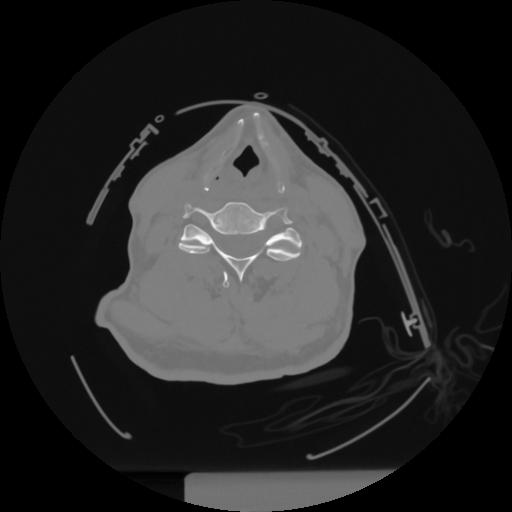

12 P.BLANDAS,,Vol,0.5,P.BLANDAS,,